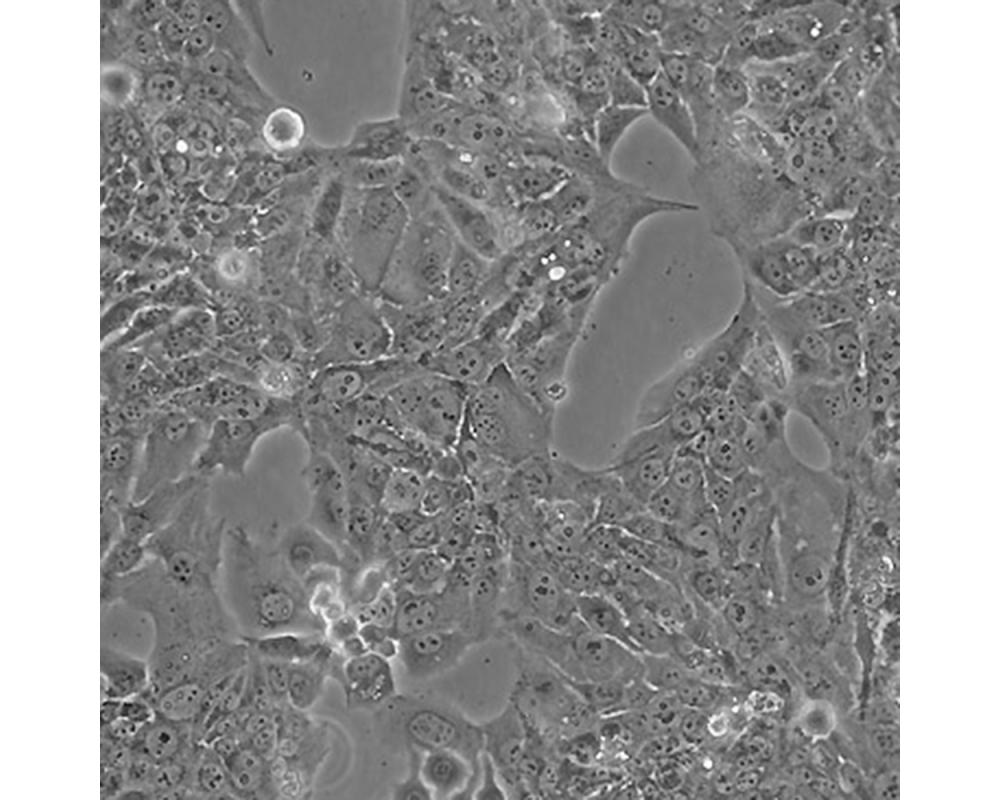

中文名稱 人胎盤絨膜癌細胞

組織來源 妊娠性絨癌

形態特征 上皮樣

生長特性 貼壁生長

特征特性 取自人絨癌腦轉移組織,在倉鼠頰囊移植傳代8年。利用移植瘤組織進行體外培養,建立細胞系。利用不同傳代方法建立了不同亞系,JEG-3是其衍生克隆。該細胞可以產生雌激素、孕激素、雌酮、雌二醇、雌三醇、hCG、胎盤催乳素、角蛋白。